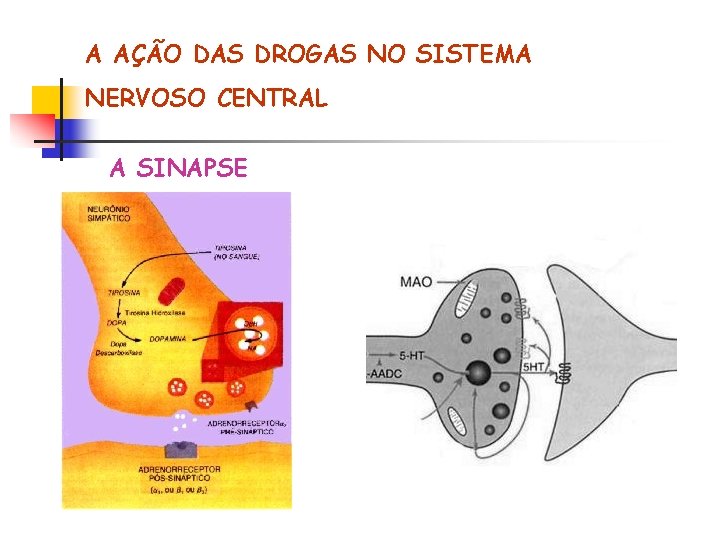

A AÇÃO DAS DROGAS NO SISTEMA NERVOSO CENTRAL A SINAPSE